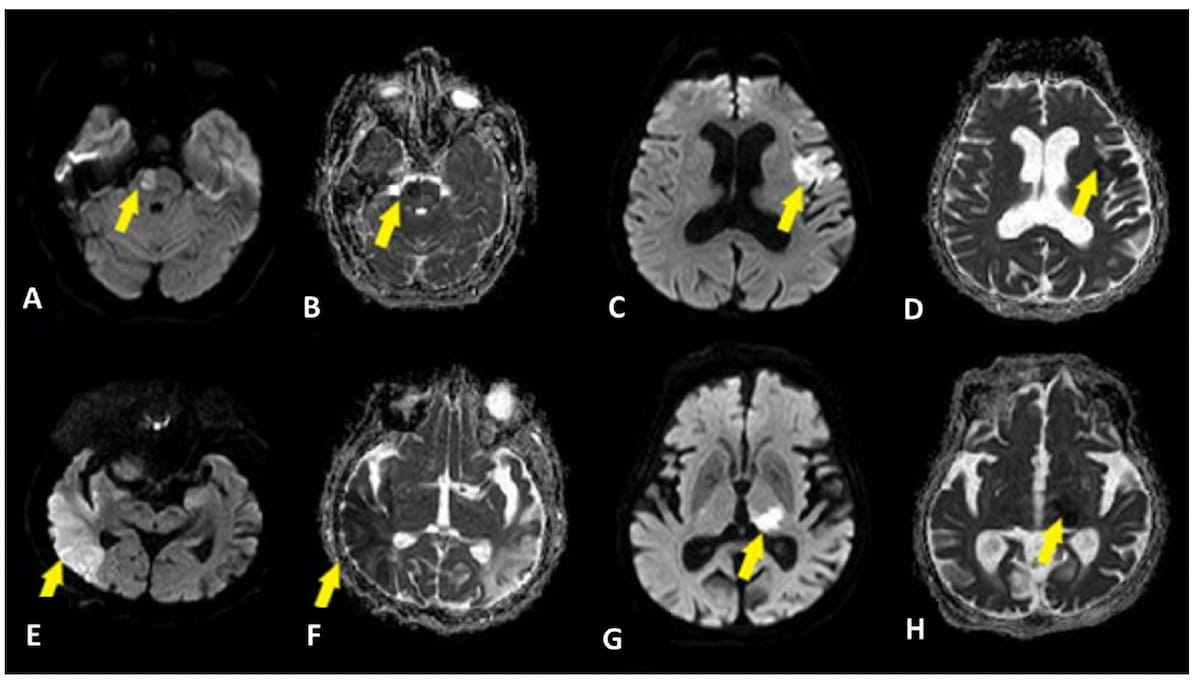

In a recently published review, radiology researchers from the University of Wisconsin discussed the potential and key considerations for applying accelerated magnetic resonance imaging (MRI) protocols in the assessment of emergent and urgent conditions.